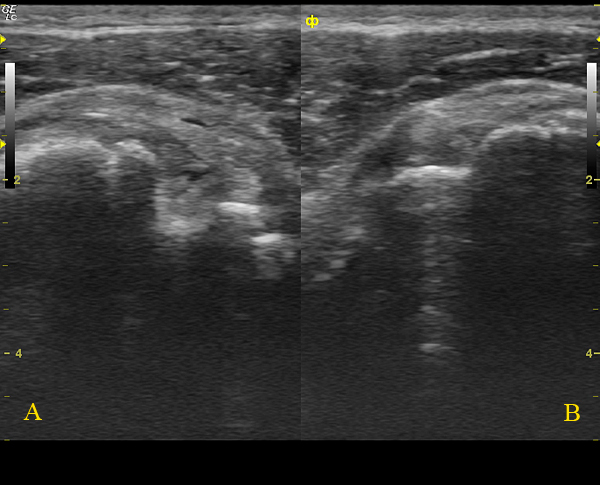

Да, на последней сонограмме В+В: А - сонограмма с патологией, В - таже проекция в здоровом противоположном плечевом суставе.

Вот такой получился у меня расклад данного уз-случая.

А:

ГП - головка плечевой кости,МБ - межбугорковая борозда, ДМ- двухглавая мышца,

розовая зона - дислоцированное на уровень малого бугорка сухожилие длинной головки бицепса,

фиолетовая зона - фрагменты поперечной связки плеча, которая образована волокнами из передней поверхности сухожилия подлопаточной мышцы, желтая зона - сухожилие надостной мышцы с участком частичного, линейного разрыва сухожилия.

В:

Сонограмма здорового контролатерального плечевого сустава, представлена для сравнения нормального расположения сухожилия длинной головки бицепса в межбугорковой борозде.